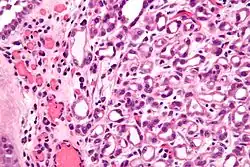

Micrograph of a nephrogenic adenoma. H&E stain.

Nephrogenic adenomas are diagnosed under the microscope by pathologists. Microscopically the tumor shows closely packed small tubular structures in edematous stroma. The tubules show considerable variation in size and shape resembling convoluted tubules of the kidney. The single layer of cells lining the tubules are cuboidal with a scant to moderate amount of cytoplasm. In some areas they may have a hobnail appearance. [2]